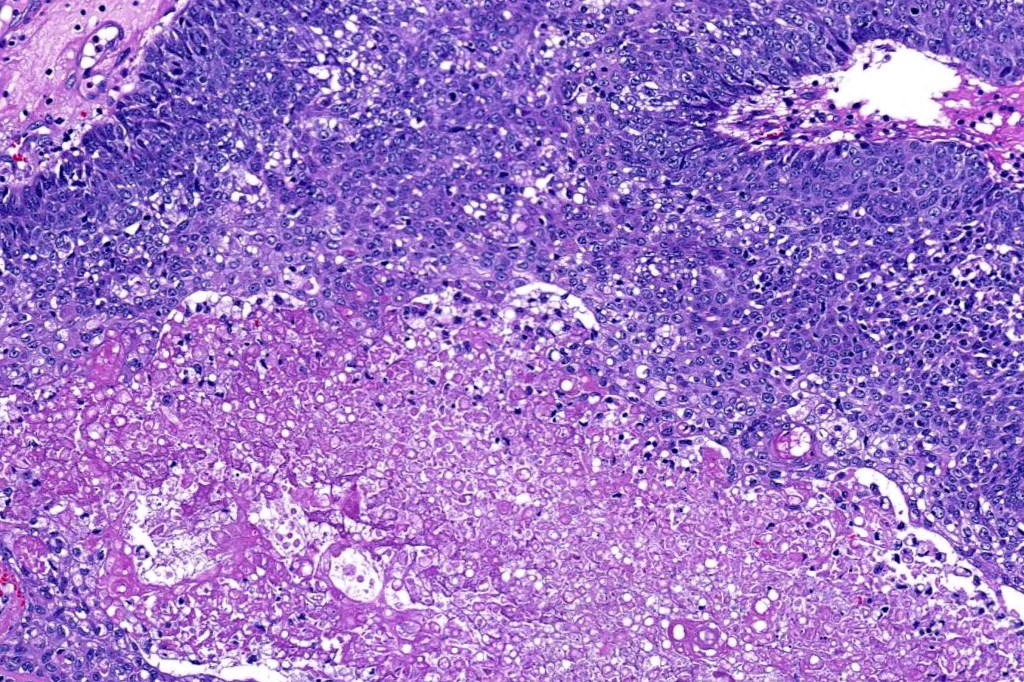

•Tumors are composed of an admixture of darkly staining basaloid cells with hyperchromatic or vesicular nuclei and more obvious sebaceous cells with eosinophilic, bubbly, multivacuolated cytoplasm frequently indenting the nucleus (scalloped)

•Often mitoses are numerous and abnormal forms evident

•Variable Lymphovascular invasion & perineural infiltration

•Focal squamous differentiation with keratinization can be present resulting in confusion with squamous cell carcinoma